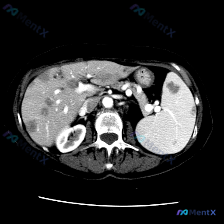

这是一张增强腹部CT横断面(软组织窗):

- 肝脏:肝左右叶弥漫分布多发、大小不一类圆形低密度灶,边缘相对清晰,部分病灶可见边缘强化/“靶征”;

- 脾脏:脾脏实质内也有类似的低密度占位病变;

- 其他:腹主动脉、肠系膜上动脉显影良好,无明显增大淋巴结,肾脏结构相对完整。